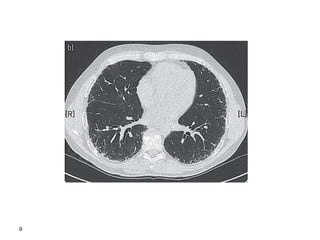

8

9

10

or cryobiopsy Thorax 2008;63(SupplV):v1– v58. doi:10.1136/thx.2008.101691 Diagnostic Algorhithm for ILD cryobiopsy